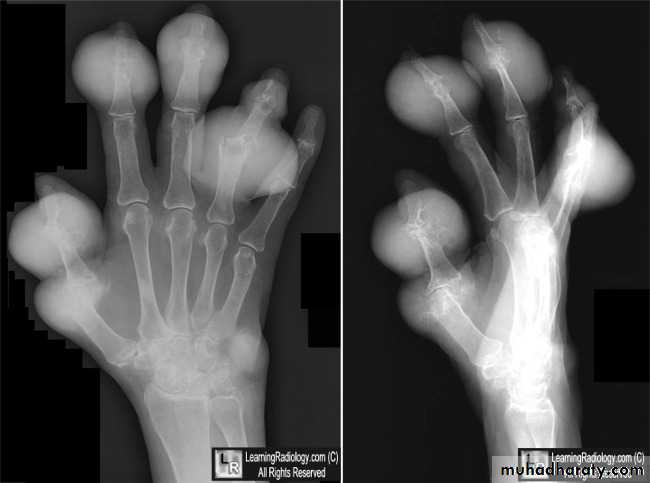

GOUT

• Heterogeneous group of entities characterized by recurrent attacks of arthritis secondary to deposition of sodium urate crystals in and around joints.• *90% of patients are male

• Radiographic features

• *Lower extremity > upper extremity; small joints > large joints

• * First MTP is most common site

• * Marginal, peri articular erosions: overhanging edge

• * Erosions may have sclerotic borders

• * Joint space is preserved

• * Soft tissue and bursa deposition

• Tophi: juxtaarticular, helix of ear

• * Erosions and tophi only seen in longstanding disease

• * Tophi calcification, 50%